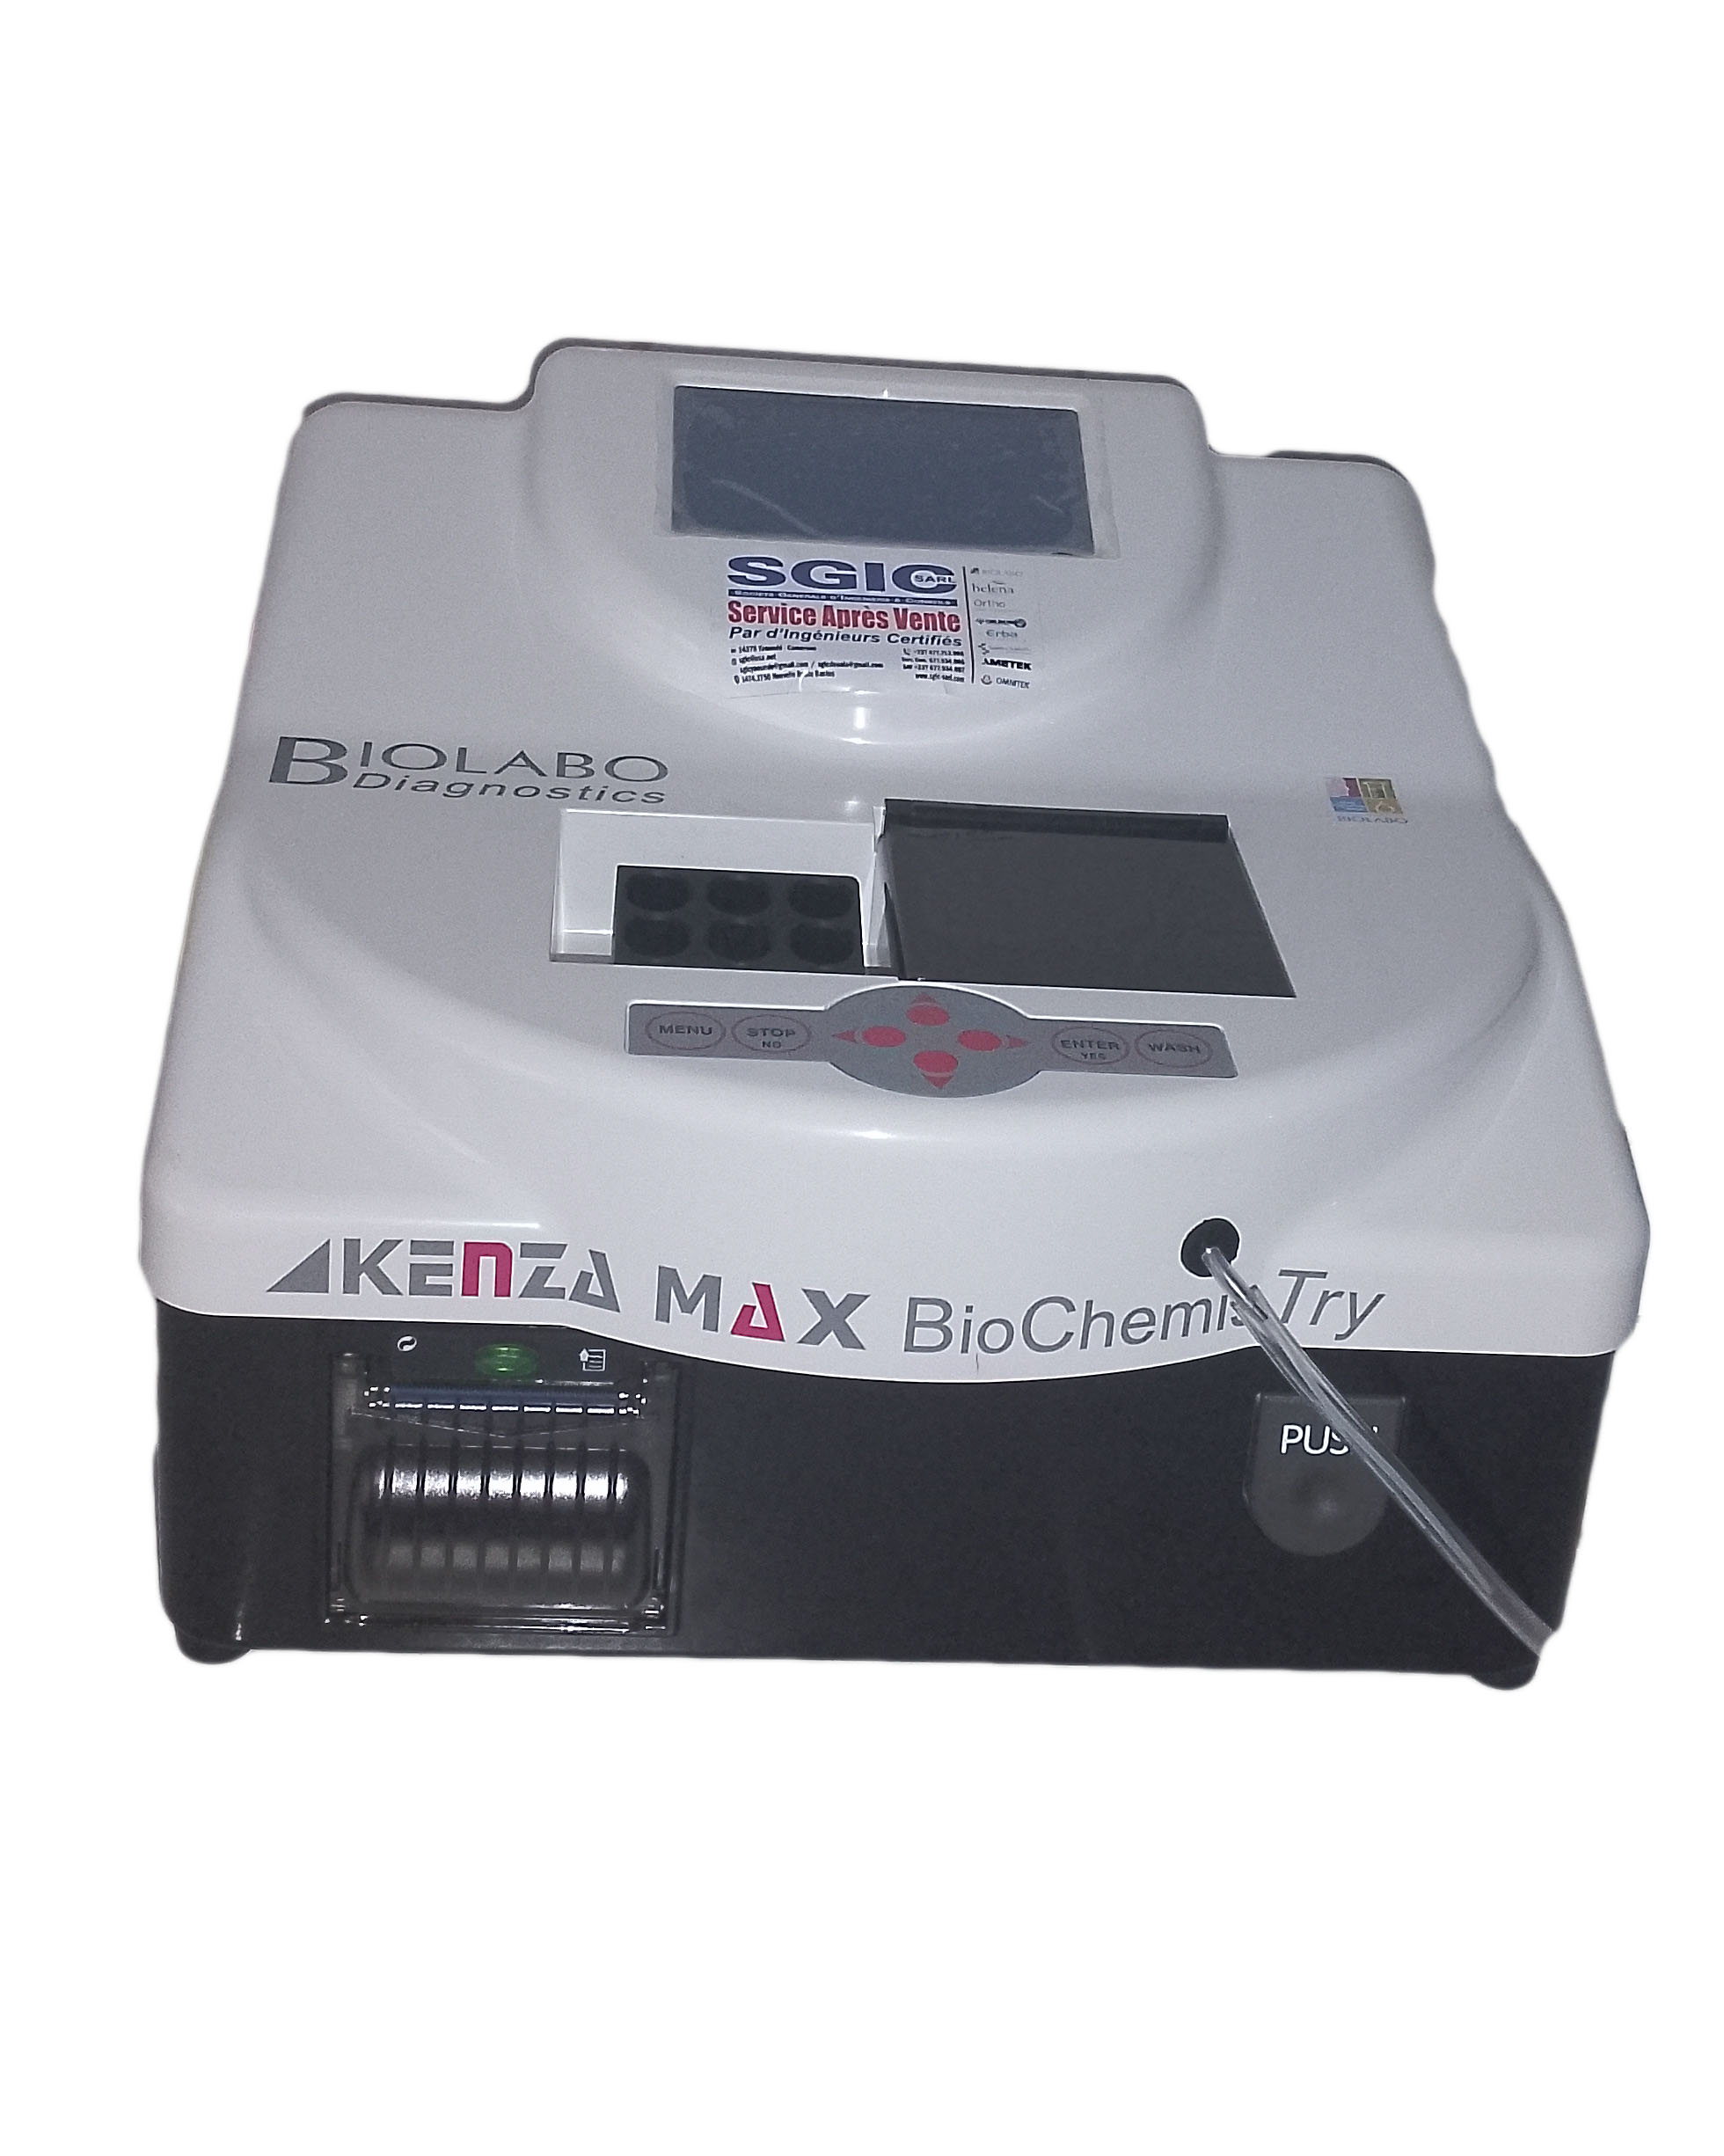

Laboratoires